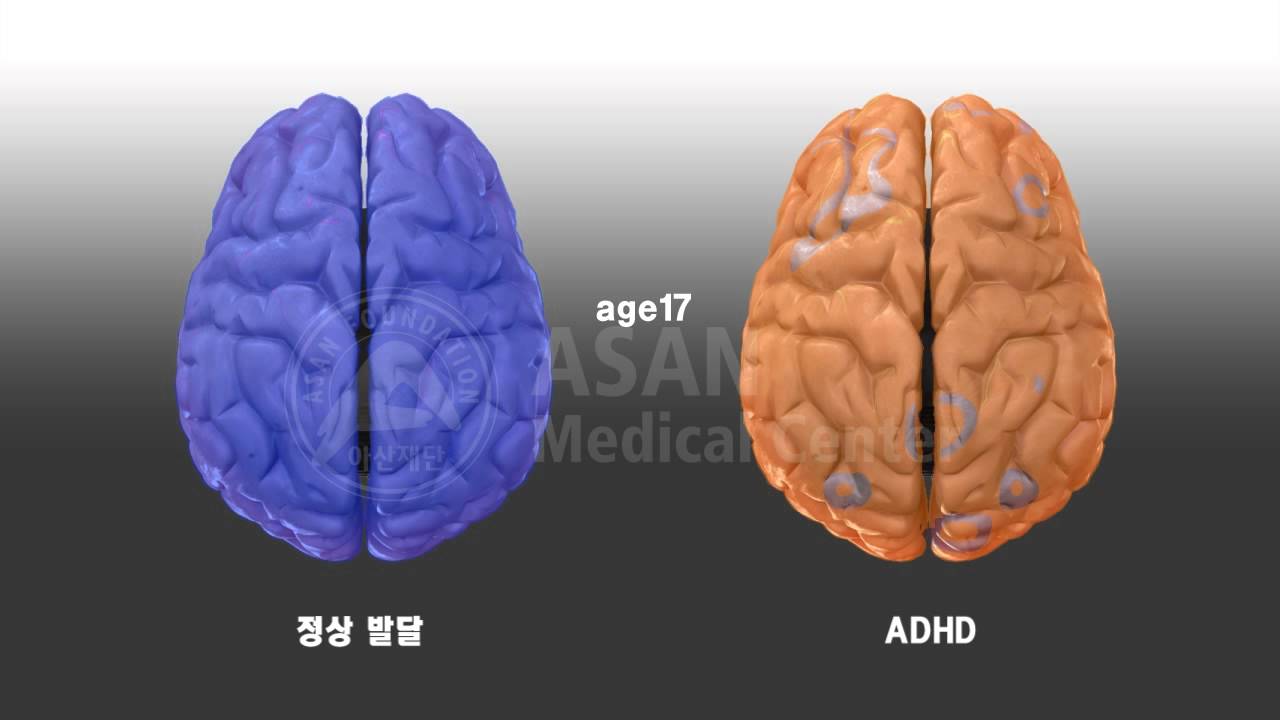

ADHD Brain Vs Normal Brain Functions Differences More

That s why it s vital to stagger the bloom times of your perennials for non stop color Use this list of spring summer and fall blooming perennials for sun and shade to start planning ADHD Brain Vs Normal Brain Differences Explained Unlike summer annuals that bloom consistently over many months, perennials generally have a window of time when their flower flushes appear. By following this guide, you can design a perennial garden that will provide four seasons of interest.

ADHD Brain Differences Stuff4Educators

Compare Normal Vs ADHD Brain YouTube

Brain Markers Of ADHD Identified In Children s MRI Scans